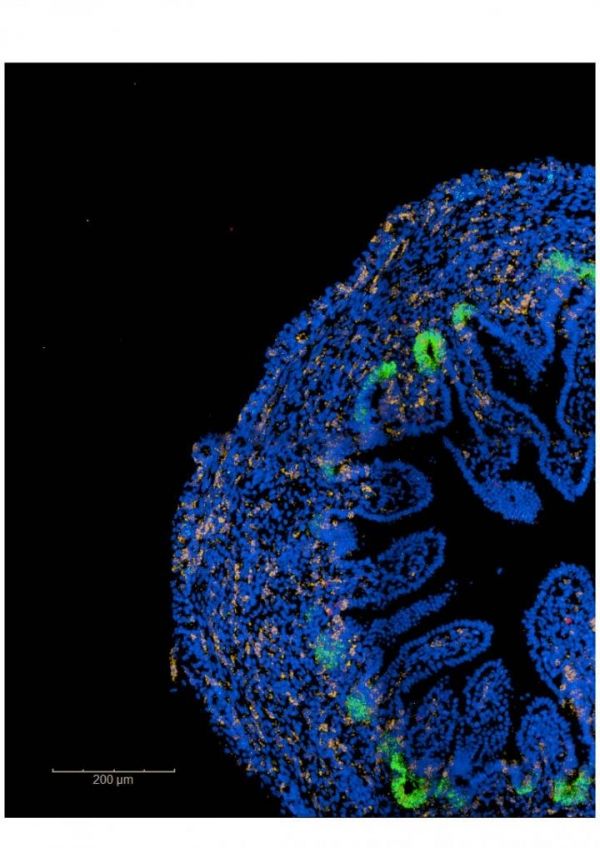

Emerging intestinal villi with green stem cells supporting their growth (Photo Credit: Kenny Roberts & Sophie Pritchard, Wellcome Sanger Institute)